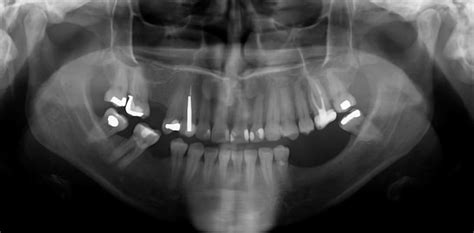

La pérdida de masa ósea se identifica mediante radiografías panorámicas y TAC dental 3D. Las imágenes 3D permiten detectar precozmente la baja densidad del hueso alveolar. Aunque la pérdida ósea puede ser imperceptible para el paciente, es crucial visitar al dentista semestralmente para detectar anomalías a tiempo.